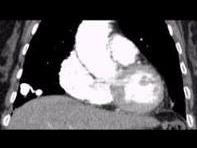

请看一组肺血管的CT增强图像,考虑最可能的诊断为 ( )A、肺动脉钙化B、肺动脉破裂C、肺动脉狭窄D、肺动脉扩张E、肺动静脉畸形

问题 请看一组肺血管的CT增强图像,考虑最可能的诊断为 ( )

选项 A、肺动脉钙化 B、肺动脉破裂 C、肺动脉狭窄 D、肺动脉扩张 E、肺动静脉畸形

答案 E